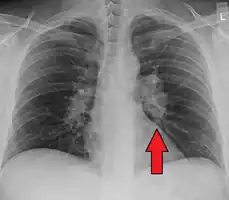

Chest X-ray showing the typical nodularity of sarcoidosis, predominantly in the bases of the lungs.